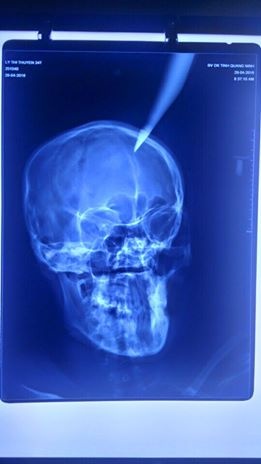

Bệnh nhân L.T.T. (24 tuổi, trú tại xã Nam Sơn, huyện Ba Chẽ, tỉnh Quảng Ninh) được chuyển từ bệnh viện địa phương đến Bệnh viện Đa khoa tỉnh Quảng Ninh vào chiều ngày 29/4 trong tình trạng nguy kịch với con dao nhọn dài khoảng 20 cm đâm giữa đỉnh đầu. Nạn nhân đang mang thai ở tháng thứ 5.

Thai phụ được đưa đến bệnh viện với con dao nhọn cắm sâu 4 cm vào đỉnh đầu . |

Kết quả chụp X-quang cho thấy phần đầu nhọn của dao cắm sâu 4 cm vào não. Theo người nhà bệnh nhân, vụ tai nạn hi hữu xảy ra khi bố chồng của chị T. sửa mái nhà đã vô tình làm rơi con dao dắt trong người xuống, cắm thẳng vào đầu con dâu đang đi qua ở phía dưới.